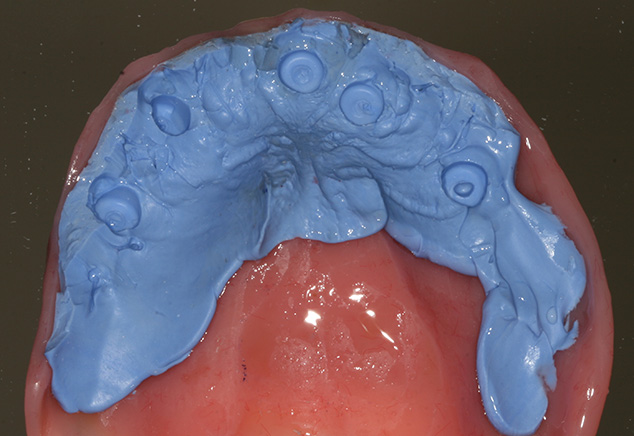

The patient was seen from Dr. Robert Levine's office for restorative records in preparation for immediate load protocol. The previously processed dentures were first checked with pressure paste to insure there was no contact of the intaglio surface with the tall healing caps. Bite registration material was then used to confirm there was no contact (Fig 9) and later will be used by the lab to articulate the models. Efforts were made to confirm the OVD (with the marked tongue depressor provided by Dr. Levine), incisal position, midline, plane of occlusion, and centric position with the prosthesis in place. Adjustments were made as needed. Photographs were acquired to document and relay information via e-mail to the lab technician. The lab will use the registration material left in the intaglio surface of the prostheses, as healing caps will be placed on the newly fabricated models. This allows the index to transfer the OVD and centric relationships with contact just on the healing caps. The soft tissue plays no role in this relationship. A bite registration was made to confirm centric relation. Healing caps were then removed and open tray impression copings were placed. If the connection between the implant abutments and the impression copings are not visualized, then x-ray confirmation of the connection is needed. Transfer Impressions were made using a custom tray and rigid impression material of choice, in this case polyether was used. Our lab courier delivered the dentures and impressions to the lab for the conversion to metal-reinforced, screw retained provisionals, which were delivered back to the restorative office within 24 hours.